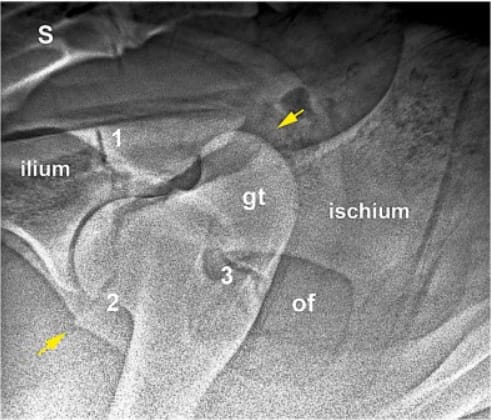

A 30°dorsolateral-ventrolateral oblique radiographic view of an acetabular fracture with ischial involvement in a 10-month-old, mixed-breed, dairy heifer. The acetabular and greater trochanter growth plates are visible. Yellow arrows indicate the course of the fracture from the ischium through the cranioventral acetabular growth plate. 1 = ilio-ischial (dorsal) part of the acetabular growth plate; 2 = ilio-pubic (cranioventral) part of the acetabular growth plate; 3 = growth plate of the greater trochanter (gt); of = obturated foramen; S = sacrum. The ischio-pubic (caudoventral) part of the growth plate is not discernible.